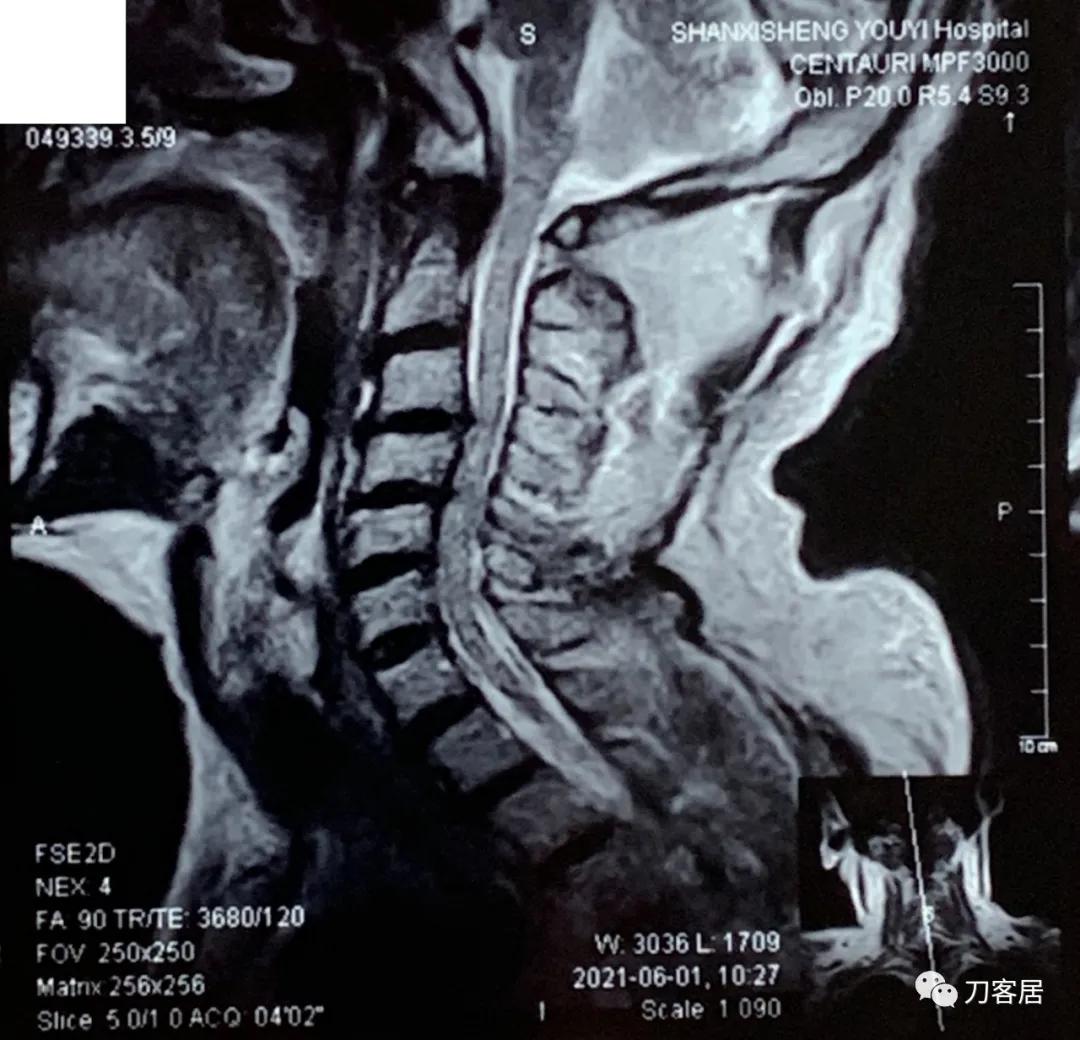

自带颈椎MRI提示颈3-4,颈4-5,颈5-6,颈6-7椎间盘突出,椎管狭窄。目前无明确上位神经损伤表现,暂不处理。骨密度提示骨量减少,但因患者的临床表现,符合骨质疏松症的表现,夜间痛明显,活动后缓解,且已高龄,虽然患者的颈椎MRI片子显示多节段椎间盘突出,椎管狭窄,比较严重, 但无明确的神经损伤表现,病理反射阴性,所以,选择保守治疗,先行抗骨质疏松,以观疗效后决定是否在未来需要手术治疗。

诊断: 骨质疏松症,颈3-7椎间盘突出,颈椎管狭窄。

2021年6月1日外院的颈椎MRI